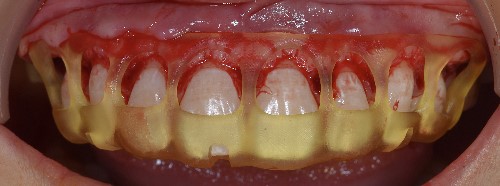

The STL files of the maxilla and teeth were manipulated using BlueSky Plan software (see Fig. 8). Subsequently, a guide was designed to facilitate osseous resection, adapting to both the teeth and the maxilla (see Fig. 9). In the surgical phase, a full-thickness flap was raised in the upper jaw, and the guide was affixed (see Figs 10 and 11). The guide snugly conformed to the bone, and its position was verified with a margin distance from CEJ set at 3 mm (see Figs 12 and 13). Postoperative results at 2 and 12 months are shown in Figs 14 and 15. The final outcomes closely resembled the Digital Smile Design (DSD) simulation conducted before treatment (see Fig. 16).